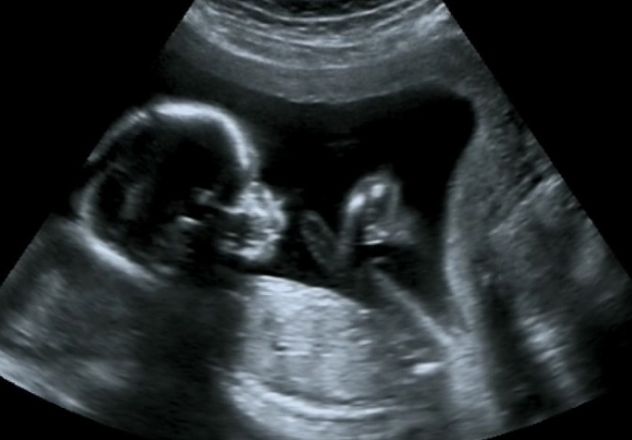

Nossas ultrassonografias são realizadas com equipamentos modernos e por profissionais experientes, garantindo diagnósticos precisos e acompanhamento detalhado. Estamos aqui para apoiar você em cada fase, com informações claras e todo o carinho que esse momento especial merece. Transvaginal, Morfológica e Ecocardiograma Fetal com quem entende de Ultrassom e de você!

Confie na nossa expertise para uma gestação tranquila e segura. Agende seu horário!